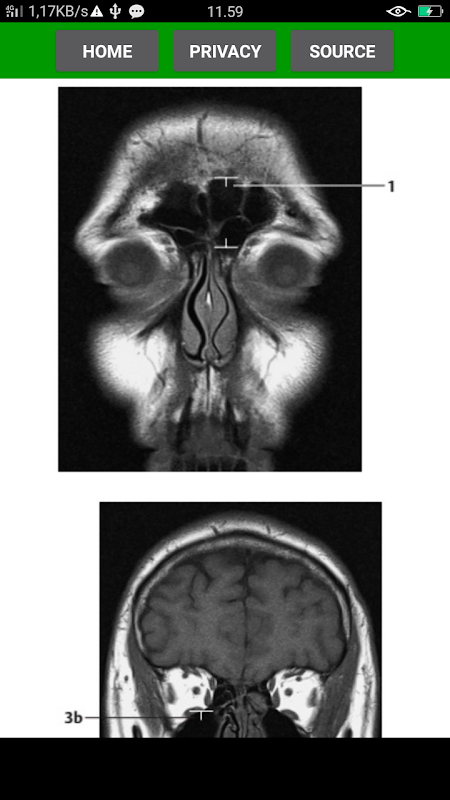

The key for any beginning radiologist who wishes to recognize pathological findings is to first acquire an ability to distinguish them from normal ones. This outstanding guide gives beginning radiologists the tools they need to systematically approach and recognize normal MR and CT images.

* Reference-quality images from the author's own teaching files show all standard normal findings as seen in CT and MRI